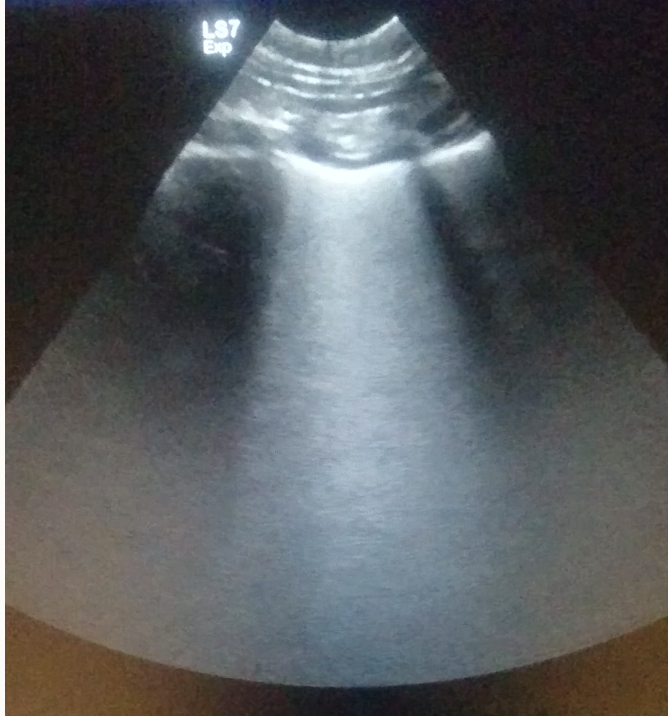

17

Q

What does a normal lung ultrasound look like?

A

How well did you know this?